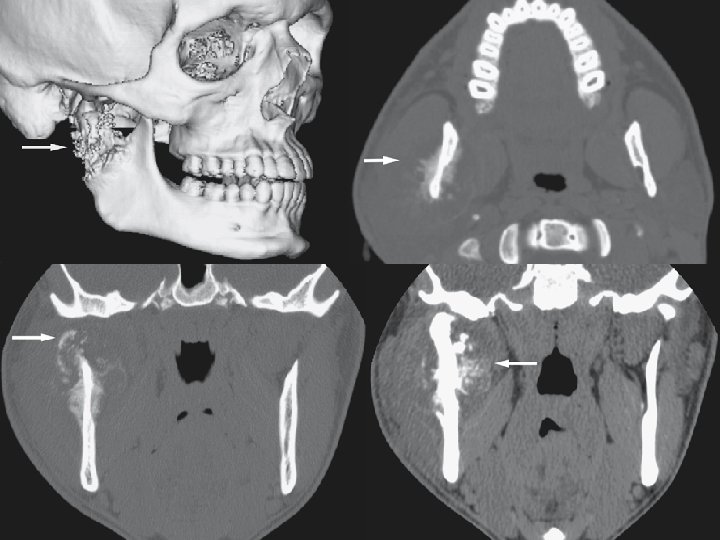

Panoramic view Coronal CT image Axial CT image Coronal T 1 -weighted post-Gd MRI